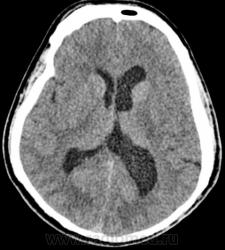

Nela. КТ головного мозга и костей. Гистиоцитоз Х (морфологическая верификация).

Пациент - молодой человек, предъявляет жалобы на головные боли и боли в шее. Болеет с 2002 года.

Гистиоцитоз Х – заболевание ретикулоцитарной системы неизвестной этиологии, морфологически характеризующееся первичной пролиферацией своеобразных гистиоцитов (клеток Лангерганса или клеток Х) и образованием в легких и в других органах и тканях гистиоцитарных гранулем и гранулематозных инфильтратов.

В понятие “гистиоцитоз Х” включают болезнь Abt–Letter–Siwe, болезнь Hand–Schuller–Christian, а также эозинофильную гранулему с разной степенью выраженности гистиоцитарной пролиферации.

Заболевание относится к системным: гранулемы могут образовываться в различных органах, но наиболее часто поражаются легкие и кости. Заболевают чаще всего люди молодого возраста, между 20 и 40 годами, большей частьюмужчины.